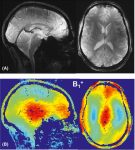

Перед вами — прижизненное МРТ человека «человека без памяти». При жизни о нем знали только инициалы — H.M., и только […]… далее

Физики из ИТМО вместе с коллегами усовершенствовали геометрию диполей — устройств, создающих магнитное поле в аппарате МРТ. Это позволило увеличить […]… далее